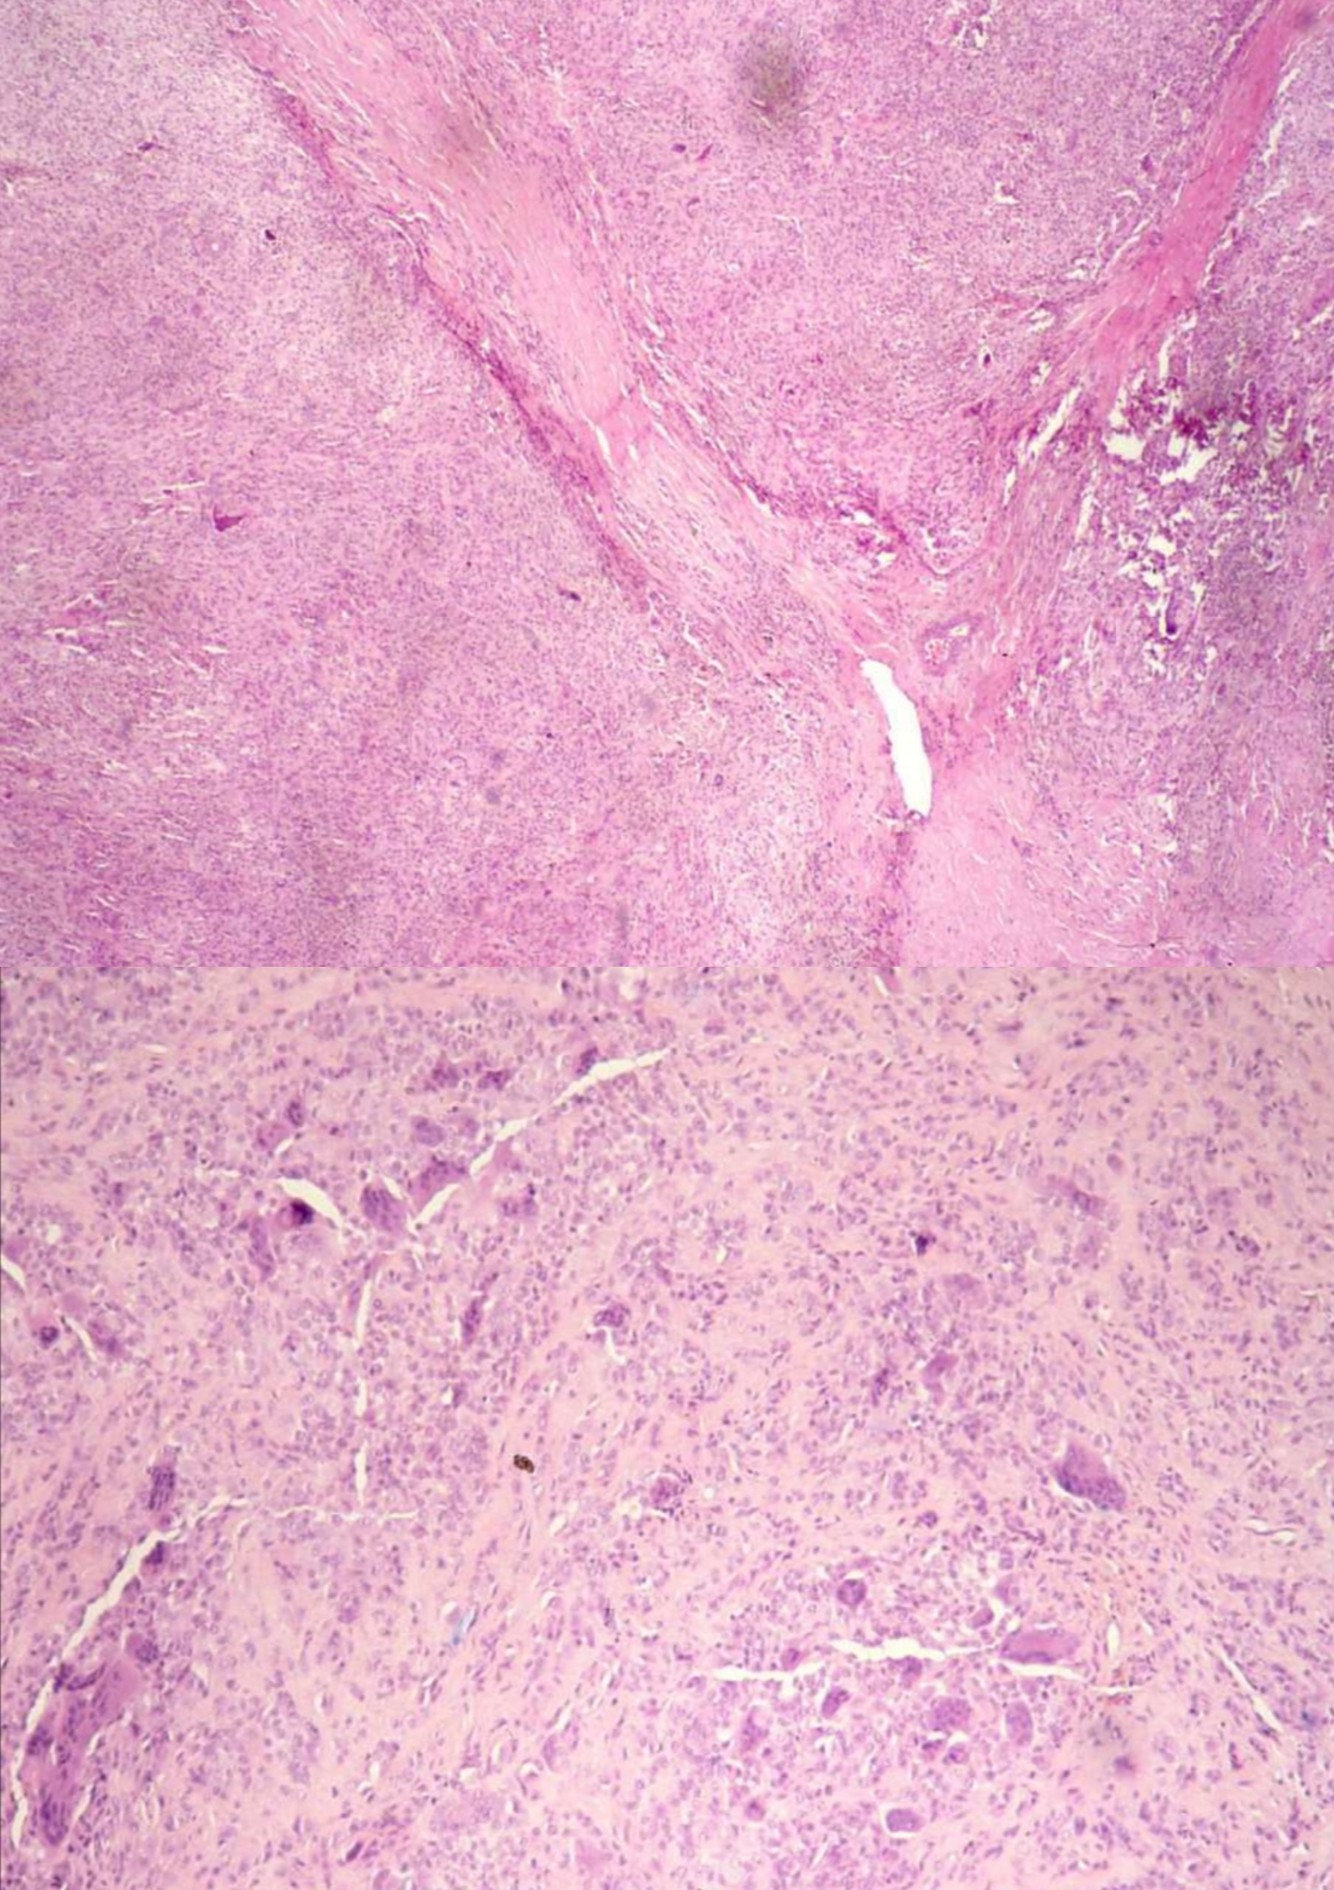

MALIGNANT PERIPHERAL NERVE SHEATH TUMOR

• S100 negative except for epithelioid MPNST.

• Definitive diagnosis of MPNST: history of neurofibromatosis, origin from major nerve trunk, areas of a benign PNST

• Variants of MPNST: Triton tumor, MPNST with angiosarcoma, epithelioid MPNST

EXTRASKELETAL MYXOID CHONDROSARCOMA

• Deep soft tissues of extremities

• t(9;22) translocation

• Multinodular growth pattern, abundant stromal mucin

• Linear cords of eosinophilic cells, sometimes rhabdoid in appearance

• Variably S100+, keratin -, EMA -

ALVEOLAR SOFT PART SARCOMA

• Genetics:

• t(X;17)

• Chromosomen1, 5, 13, 17 abnormalitys

• Clinical:

• Deep soft tissue of oral cavity, pharynx, mediastinum, thigh/leg

• Usually young females

• Highly malignant, although clinical course is slow/indolent

• Metastases up to 30 years later to veins, lungs, other

• Lung metastases may be presenting feature

• Gross:

• Well circumscribed, large, gray-yellow, hemorrhage, necrosis

• 2-14 cm

• Histology:

• Well defined nests of cells separated by fibrous stroma

• Alveolar pattern if cells discohesive

• Composed of large polygonal cells with granular eosinophilic cytoplasm, vesicular nuclei, prominent nucleoli

• Vascular invasion common; also characteristic rod-shaped crystalloids

• No/rare mitotic figures, minimal pleomorphism

• Positive: TFE3, PAS+ diastase resistant needle-like structures, MyoD1 (cytoplasmic only)

• Prognostic impact:

• Size, presence of 17q25 abnormality, AJCC stage, age

• Diff DX: metastatic renal cell ca, paraganglioma